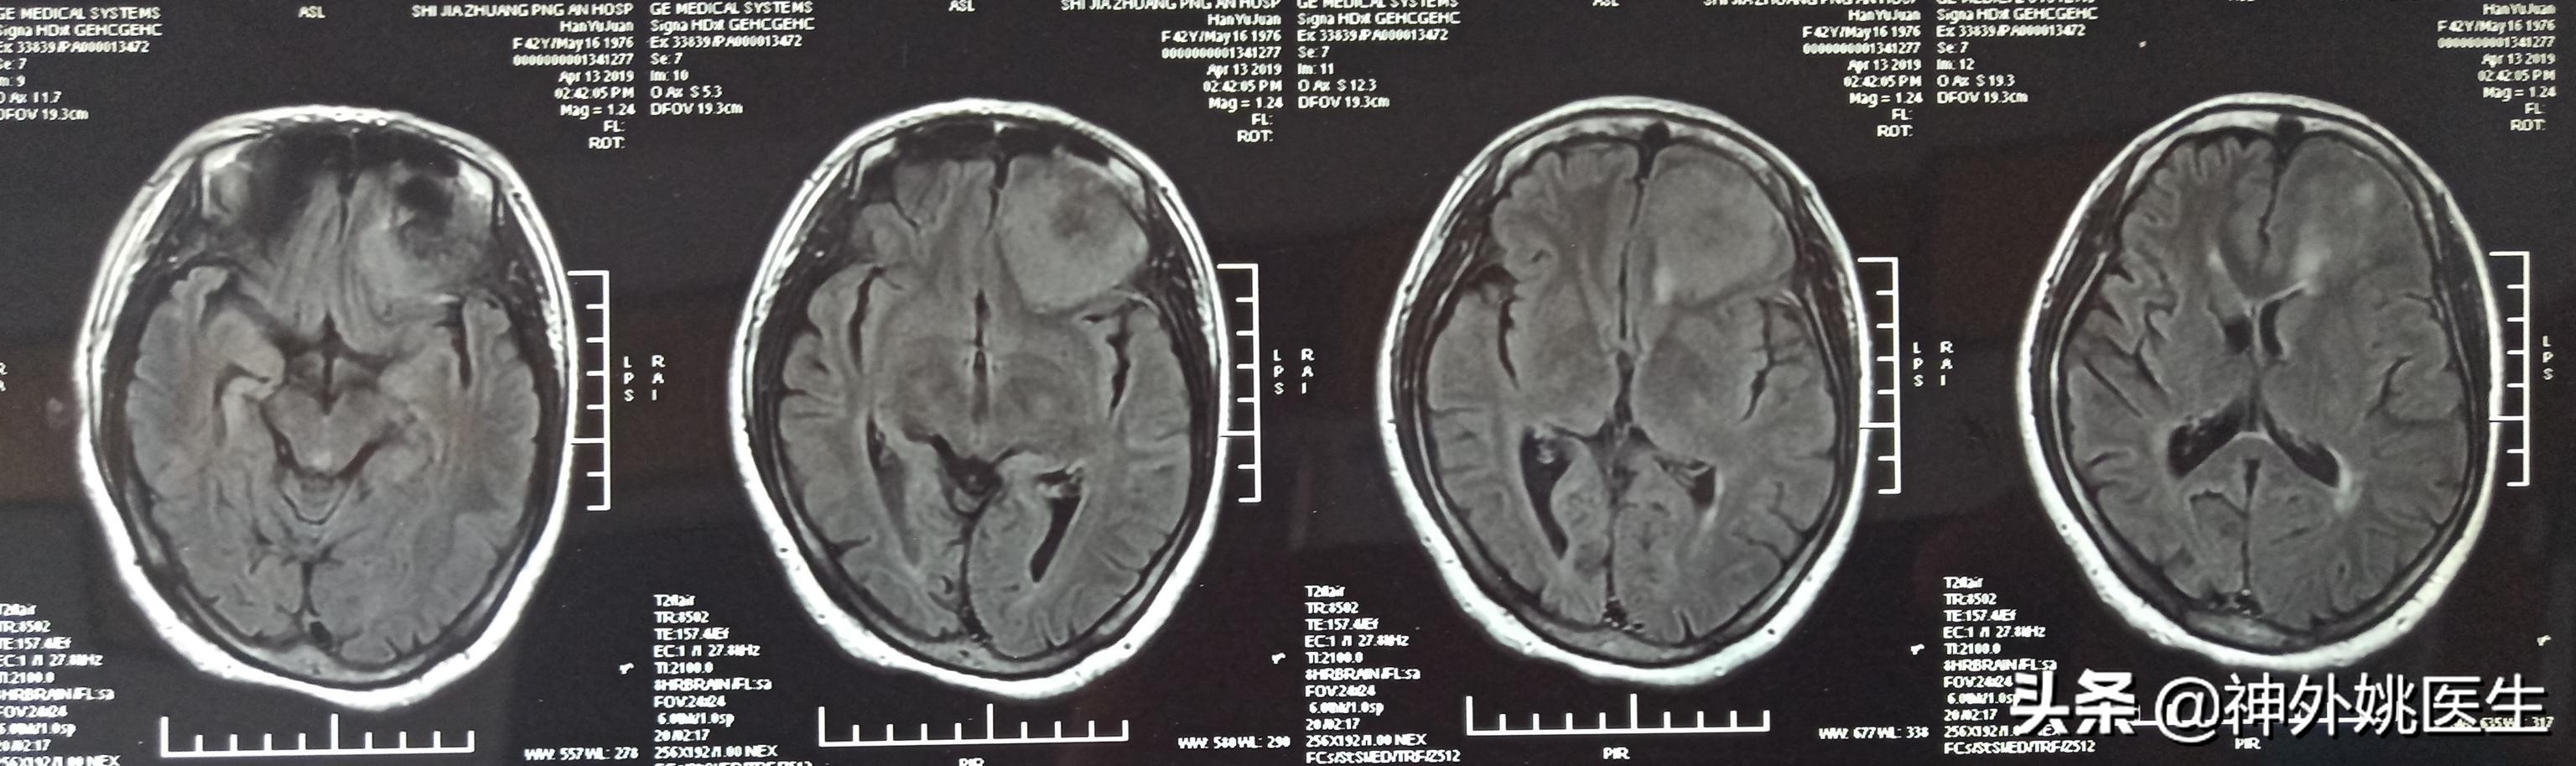

头MRI检查:1、左额部脑膜瘤。2、左侧放射冠区腔隙性脑梗死。(图3-7)

图3 T1像病变呈稍长T1信号。

图4 T1像病变呈稍长T2信号。

图5 T2Flair像病变呈稍高T2信号。

图6 增强扫描可见病变呈不均匀强化。

图7 病变基底位于颅底硬膜,可见脑膜尾征,病变大小约3.8cm x 4.1cm x 2.9cm。